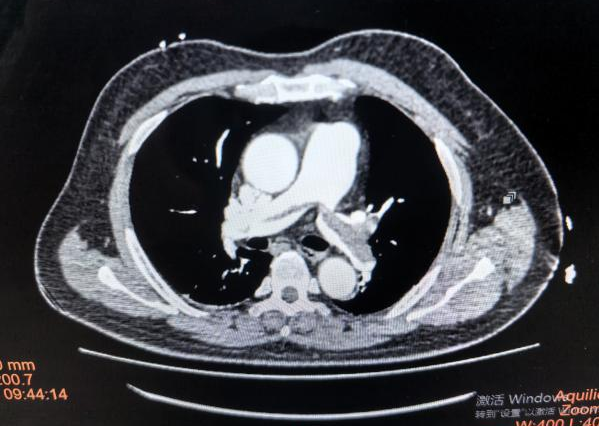

一位62岁的男性患者,因“重症肺炎、双下肺实变”入院,同时合并急性心肌梗死,病情极为危重,需行气管插管机械通气。面对患者双肺通气严重不均的状况,常规影像学检查难以实时反映其动态变化。关键时刻,EIT监测发挥了重要作用。

监测图像清晰显示:患者双下肺区域通气显著减低,通气分布极不均匀,局部存在明显的肺膨胀不良,这与影像学显示的双下肺实变表现高度吻合。在EIT的实时、可视化指导下,科室团队能够精准地调整呼吸机参数,优化肺复张策略与体位管理,并在治疗过程中兼顾心脏功能,进行综合施治。